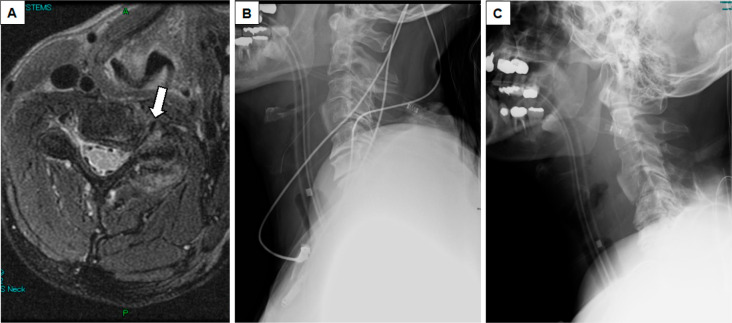

Abstract Image